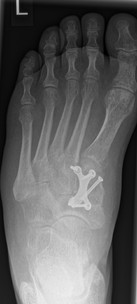

Im Rahmen einer Verlaufskontrolle zeigte sich ein Schraubenbruch als Zeichen einer fehlenden Durchbauung der Arthrodese.

3.- April 2017: Schraubenbruch